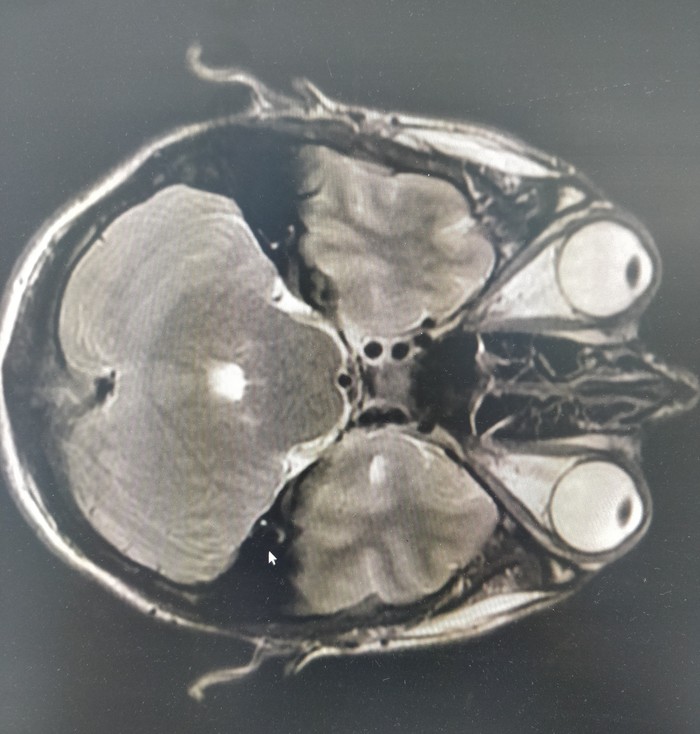

2. Часто получается такая дичь)